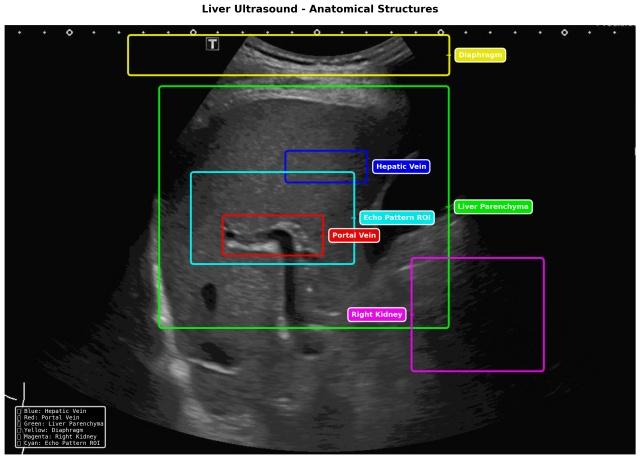

SmartLiva ทำงานโดยอัปเกรดภาพอัลตราซาวด์ขาวดำธรรมดา อัปโหลดผ่านเว็บได้ทั้งบนคอมพิวเตอร์หรือแท็บเล็ต ระบบจะปรับภาพให้ชัด คัดเฉพาะบริเวณเนื้อตับที่ต้องวิเคราะห์ ทำให้ภาพดูเข้าใจง่ายขึ้น ด้วยการไฮไลต์เป็นสี (เช่น ตับเป็นสีแดง ไขมันเป็นสีเหลือง) เพื่อเห็นความผิดปกติได้ทันที AI จะประเมิน 3 เรื่องพร้อมกัน คือ ระดับพังผืด/ความแข็งของตับ (F0–F4), ตรวจหาความผิดปกติของเนื้อเยื่อ เช่นถุงน้ำหรือมะเร็งตับ ตรวจหาพยาธิใบไม้ตับ ทั้งประมวล วิเคราะห์ สรุปผลออกเป็นรายงานพร้อมภาพประกอบและคำอธิบายที่คนทั่วไปเข้าใจได้